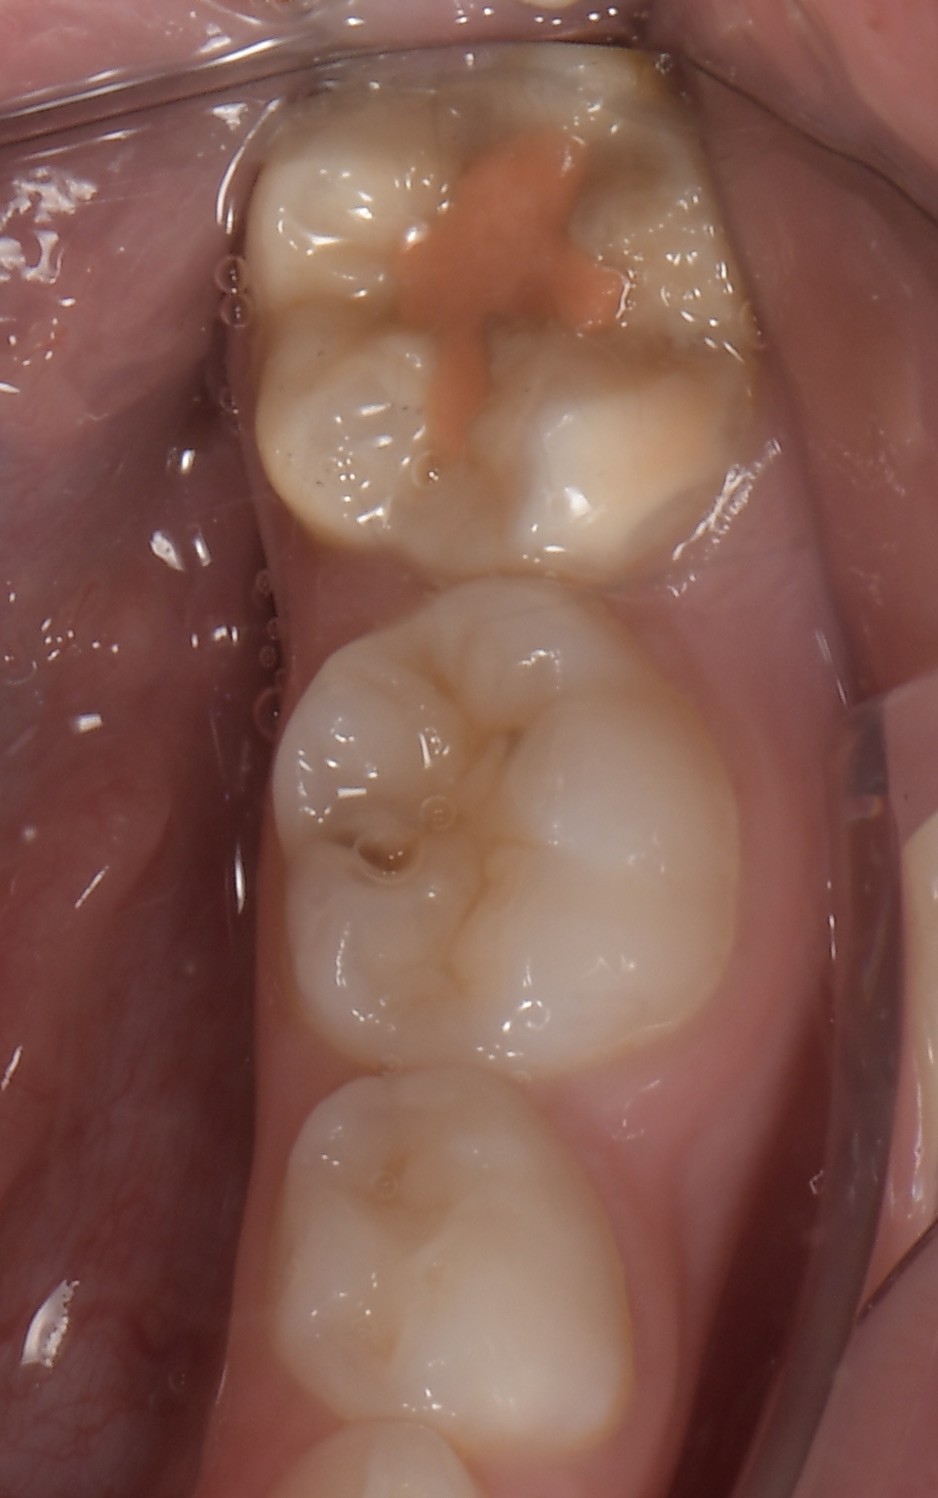

Le congrès de l’EAPD (Académie Européenne d’Odontologie Pédiatrique) a défini des critères de diagnostic en 2003. A savoir des opacités délimités, des fractures post-éruptives, des restaurations atypiques ainsi que que des extractions des molaires. (3) Le diagnostic différentiel doit surtout s’établir entre des amélogénèses imparfaites et des hypominéralisations d’origine traumatique pour les dents antérieures. Cliniquement, les dents vont présenter des colorations blanches ou brunes opaques sur une partie ou sur toute la surface de la dent (Figures 1-2-3-4).

formation dentaire pédodontie Figure 3.

Cette atteinte peut être soit légère (émail blanc, opaque), soit modérée (coloration jaune, brune, surface crayeuse et effondrement postéruptif de l’email ou PEB) ou enfin sévère (atteintes associées à des pertes de substances importantes). De plus, l’intégrité de la dent peut être aussi touchée. Plus la MIH est sévère et plus le manque d’émail sera important donc plus les sensibilités/douleurs seront importantes aussi. Cette sévérité varie en fonction des personnes, mais également au sein des dents d’un même individu : on parle d’atteinte asymétrique. Toutes les dents ne sont pas toutes touchées de la même façon, et ne nécessiteront donc, pas les mêmes types de soin.

Figure 3-4 : Molaires atteintes de MIH (HSPM + MIH pour la figure 3)